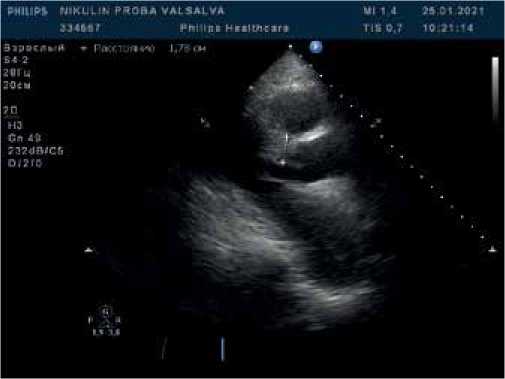

Рис. 1. В-режим. Парастернальная позиция по длинной оси ЛЖ. Асимметричная гипертрофия миокарда ЛЖ с утолщением миокарда в базальном сегменте.

Рис. 3. В-режим + CW-режим. Апикальная 5-камерная позиция. Исследование кровотока в ВТЛЖ при поведении пробы Вальсальвы. Прирост систолического градиента, максимальный систолический градиент 82,8 мм рт.ст.